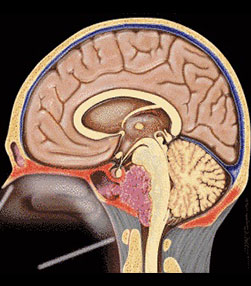

- Brain tumors - More than 1800 including pituitary, posterior fossa, intraventricular lesions, suprasellar lesions and intrinsic brain tumors

- Endoscopic brain surgeries - More than 300 endoscopic third ventriculostomies, 30 ventricular tumors.